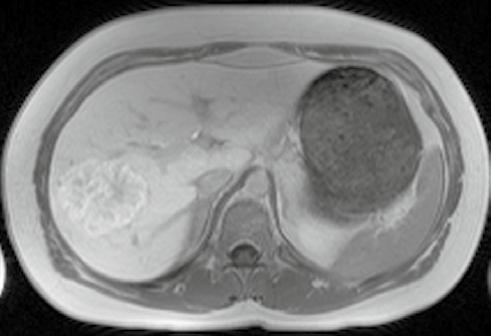

Op de beelden was te zien dat de afwijking in de lever goedaardig was, waardoor een operatie niet noodzakelijk bleek.

Dankzij de bijkomende MRI kwamen de artsen te weten dat er niet één, maar drie letsels waren.

Letsel bleek goedaardig Er was een tweede en derde tumor

Prof. dr. Dirk Ysebaert, diensthoofd hepatobiliaire, transplantatie en endocriene heelkunde: ‘In een regi onaal ziekenhuis ontdekten artsen bij een vrouw van 36 een levertu mor. Ze werd doorverwezen naar onze dienst voor een leveroperatie.’ Samen met radioloog dr. Bart Op de Beeck, kliniekhoofd Body imaging, bekeek Ysebaert de oorspronke lijke beelden. ‘We besloten om niet meteen te opereren, maar eerst te bepalen of de afwijking goed of kwaadaardig was, via een MRI met levercontrastmiddel.’

Uit de nieuwe scan bleek dat het

om een goedaardige afwijking ging. ‘In dat geval was het niet nodig om de dame te opereren. Een goedaardige afwijking kan in principe geen kwaad. We hebben de dame opgevolgd, en ook na drie jaar was de afwijking ongewijzigd.’ Een grote opluchting voor de vrouw in kwestie. Ysebaert: ‘Bij een operatie zouden we bijna de helft van de lever hebben moeten wegnemen.

Dankzij de geavanceerde beeld vorming die we als universitair ziekenhuis kunnen aanbieden, hebben we dus een zware operatie kunnen vermijden.’